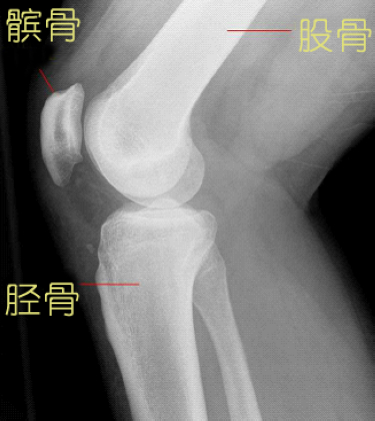

膝关节X光片(矢状面)。

" Y3 |4 L" E. d% a膝关节作为人体最大最复杂的关节,由股骨下端、胫骨上端和髌骨共同构成。其中胫骨上端基本上是一个平面,而股骨下端的关节面则是一个椭圆形,两个关节面一圆一平,并不完全贴和,所以需要半月板来帮助关节面完整贴和[2]。+ ]# \7 D5 p. k; P